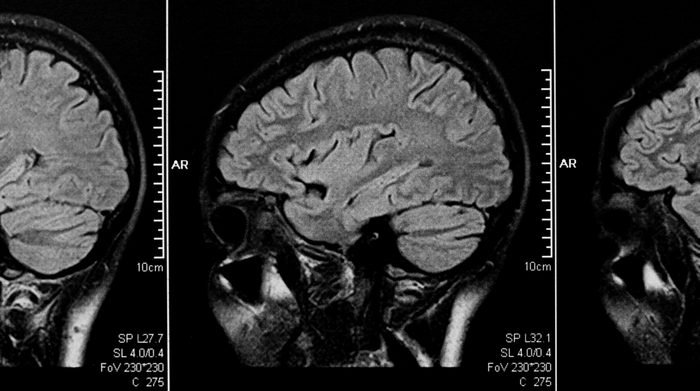

Exercising now will slash your risk of dementia

Move it or lose it, literally. This is the main message of a study in Neurology that found women who are physically fit at middle age are nearly 90 percent less likely to develop dementia decades later, compared to women who are moderately fit. “These findings are exciting because it’s possible that improving people’s cardiovascular fitness in middle age could delay or even prevent them from developing dementia,” says study author Helena Hörder, PhD, of the University of Gothenburg in Sweden, in a news release. But, she cautions, “this study does not show cause and effect between cardiovascular fitness and dementia, it only shows an association. More research is needed to see if improved fitness could have a positive effect on the risk of dementia and also to look at when during a lifetime a high fitness level is most important.”

Dementia is not a given

More than one-third of dementia cases could be prevented or significantly delayed by addressing lifestyle-based risk factors such as learning to eat right and engaging in regular exercise, according to the newly launched health initiative, Be Brain Powerful: A Campaign for Women’s Brain Health. Here are 50 everyday habits that can reduce your risk of dementia.

Alzheimer’s is a woman’s issue

Almost two-thirds of Americans with Alzheimer’s are women, and more than 60 percent of Alzheimer’s and dementia caregivers are women, according to Jill Lesser, the president of Women Against Alzheimer’s. “Women are very interested in brain health and very aware of brain health and the issues surrounding cognitive decline, but are very confused about what to do about it and still very scared,” she says. The 30-Day Brain Health Challenge involves emailing simple tips on boosting brain health daily for 30 days to get women started on the right path.